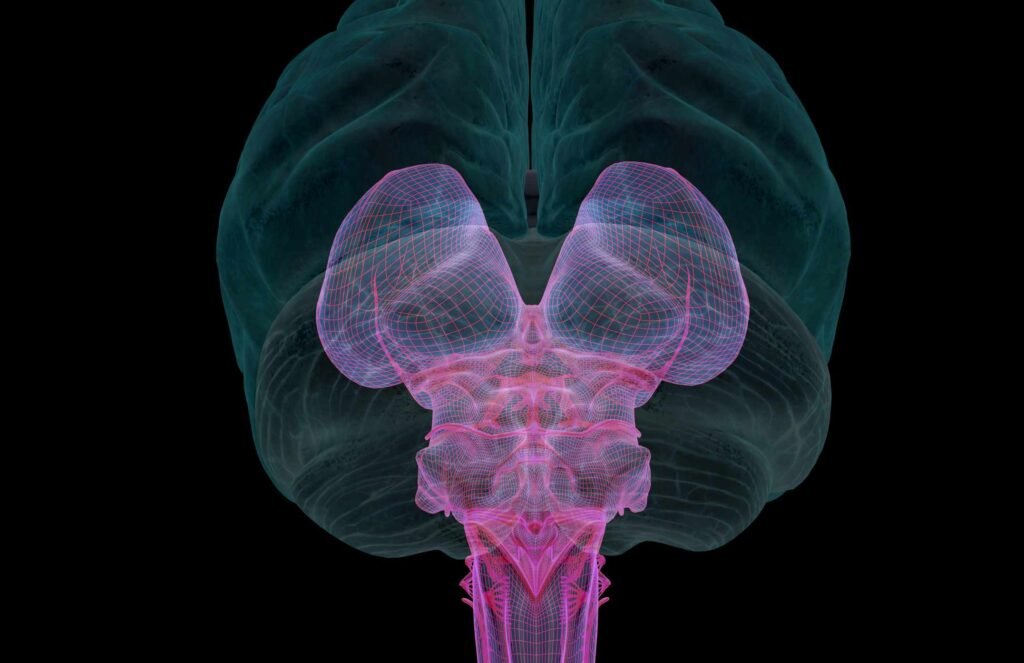

Our nervous system is a complex structure that gathers information from all over our body and coordinates activity. There are two main parts of the nervous system: the central nervous system and the peripheral nervous system.

One nerve is of particular interest to Dr. Stephen Porges, Ph.D. Dr. Porges is a distinguished university lecturer, scientist, and developer of what is referred to as The Polyvagal Theory. The vagus nerve is the tenth cranial nerve, a very long and wandering nerve that begins at the medulla oblongata, a part of the brain located in the lower part of the brain just above where the brain connects with our spinal cord.

There are two sides to this vagus nerve, the dorsal (back) and the ventral (front). From there, the two sides of the vagus nerve run down throughout our body. They are considered to have the widest distribution of nerves within the human body.